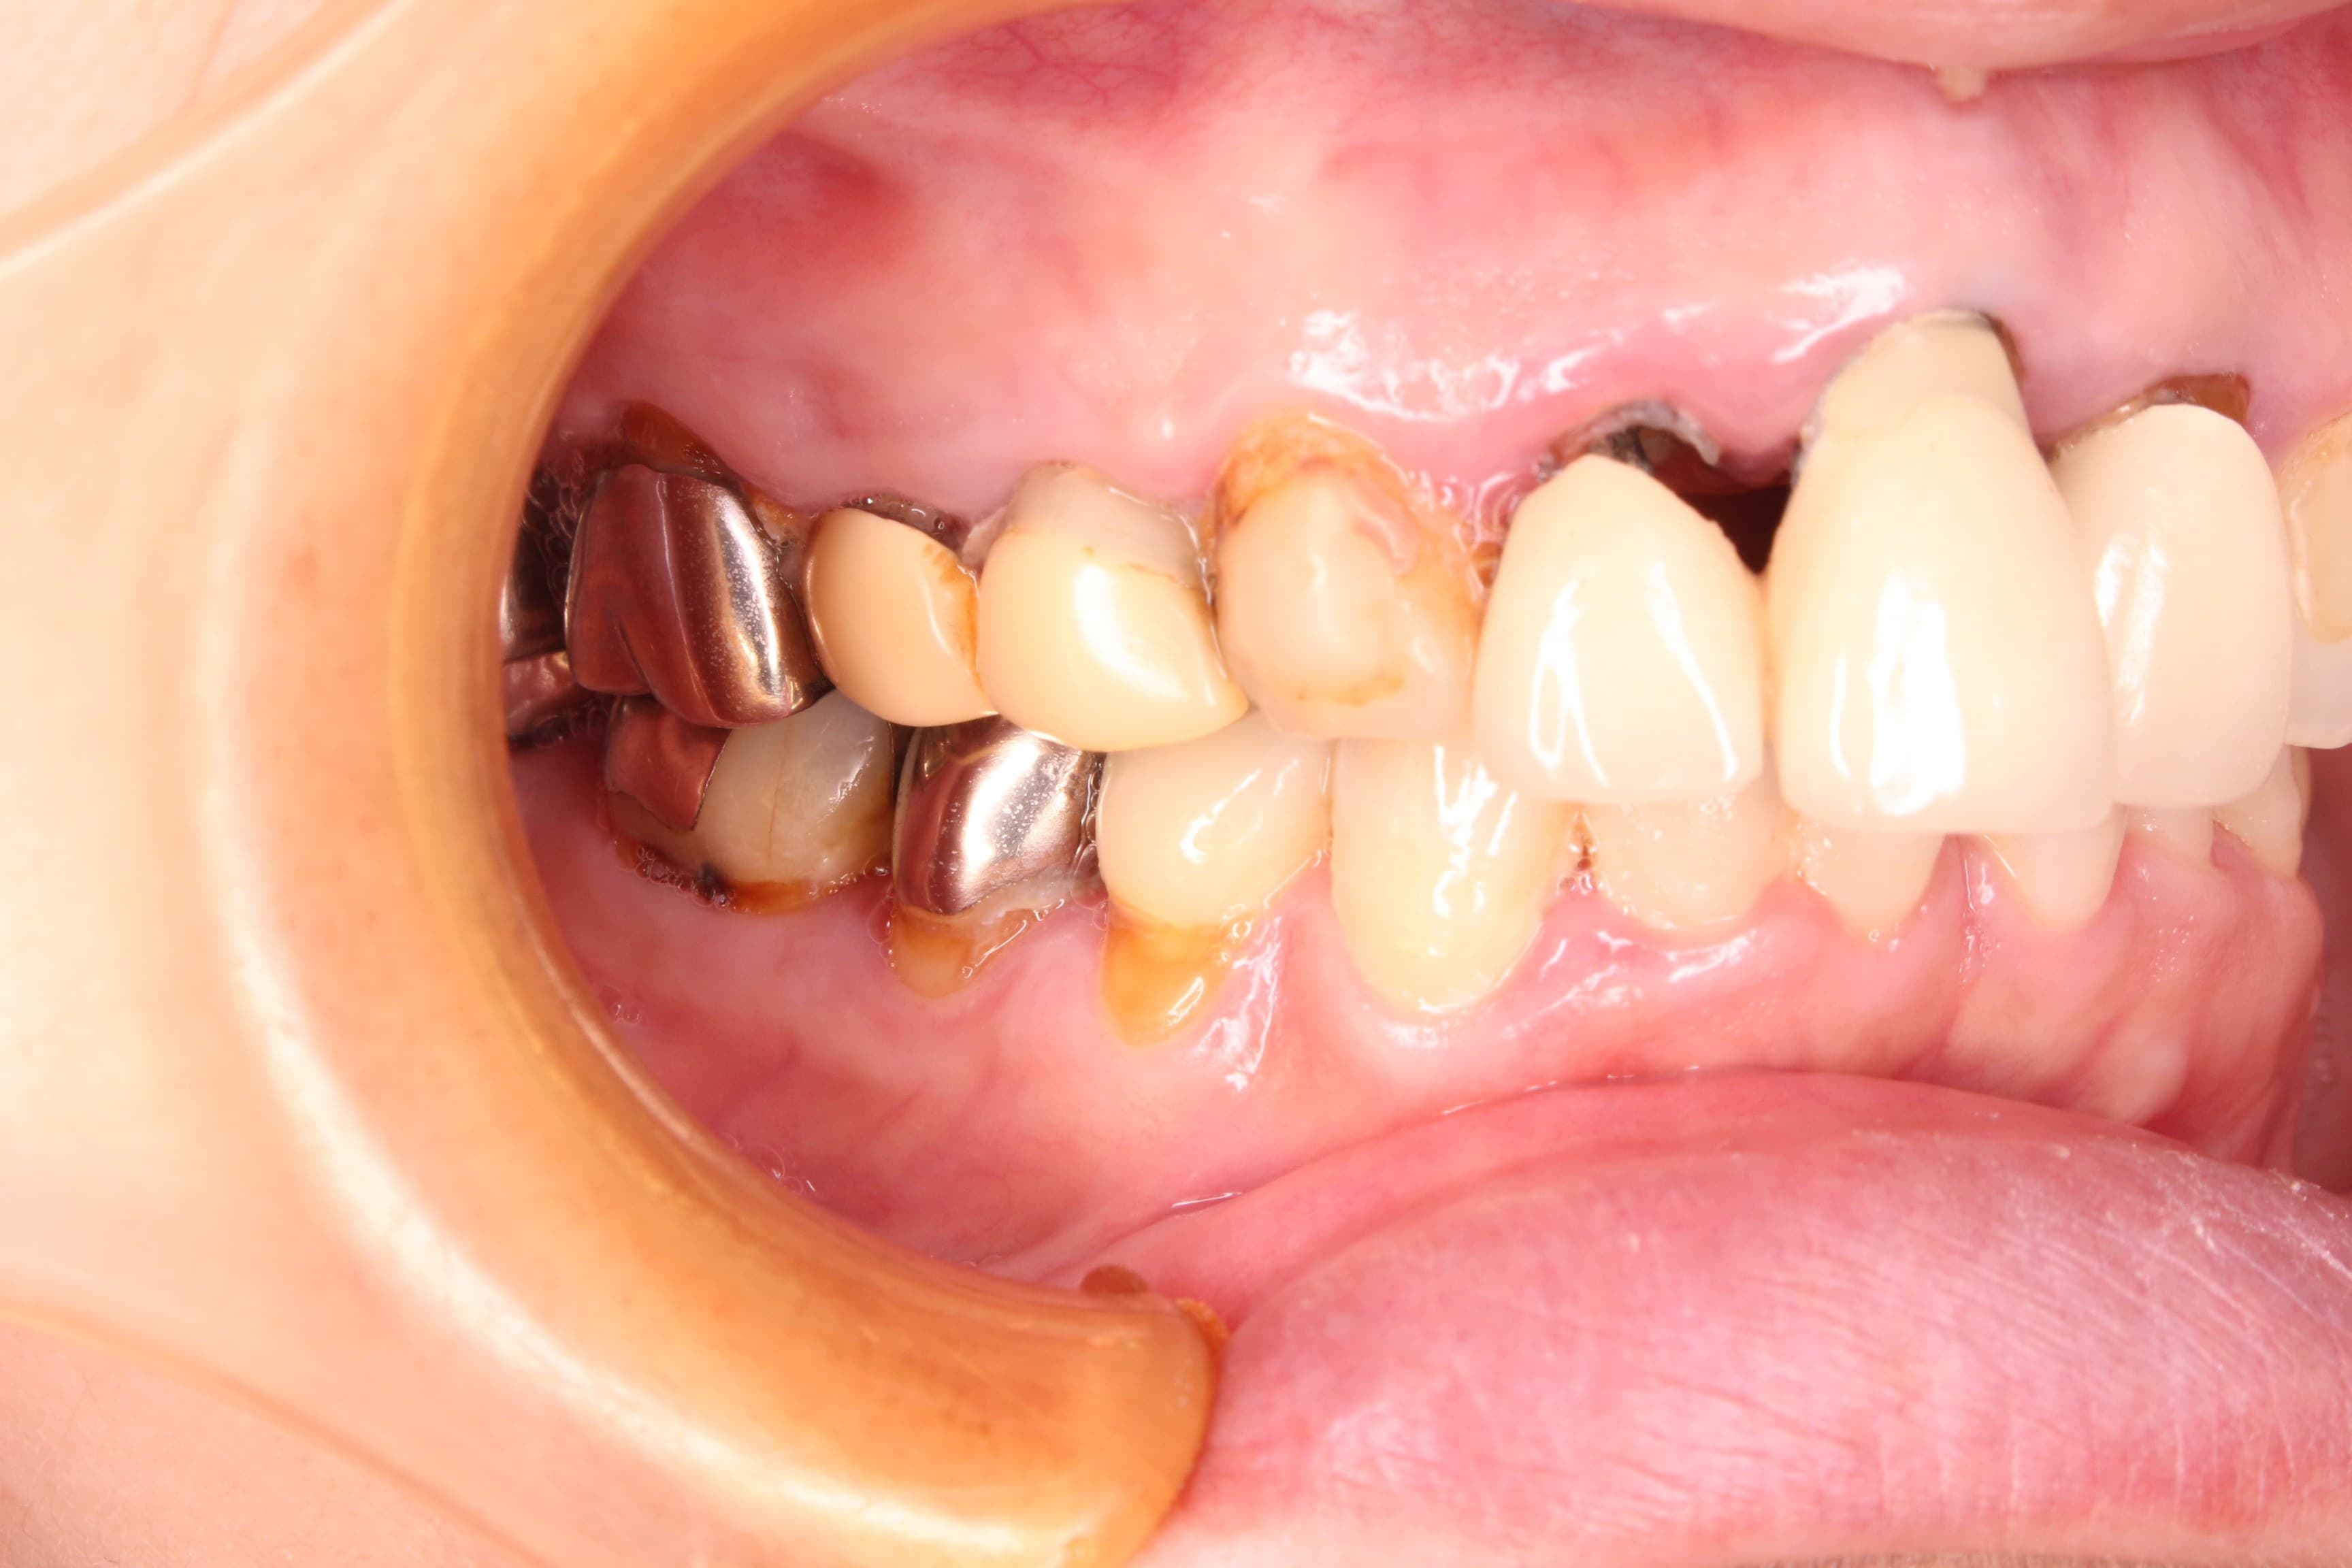

今回ご紹介する歯周専門治療のケースは、50代女性の方です。

虫歯の治療を希望されて来院されました。

口腔内の状態は、虫歯も大きく進行し、歯周病のコントロールもされておらず、出血やプラーク、歯石等の感染物質も大量に付着していた為、虫歯の治療ができる状態ではありませんでした。